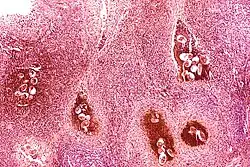

Multiple colon polyps within the colon of an individual with familial adenomatous polyposis

Although there are over 50 identifiable hereditary forms of cancer, less than 0.3% of the population are carriers of a cancer-related genetic mutation and these make up less than 3–10% of all cancer cases.[3] The vast majority of cancers are non-hereditary ("sporadic cancers"). Hereditary cancers are primarily caused by an inherited genetic defect. A cancer syndrome or family cancer syndrome is a genetic disorder in which inherited genetic mutations in one or more genes predisposes the affected individuals to the development of cancers and may also cause the early onset of these cancers. Although cancer syndromes exhibit an increased risk of cancer, the risk varies. For some of these diseases, cancer is not the primary feature and is a rare consequence.

Many of the cancer syndrome cases are caused by mutations in tumor suppressor genes that regulate cell growth. Other common mutations alter the function of DNA repair genes, oncogenes and genes involved in the production of blood vessels.[12] Certain inherited mutations in the genes BRCA1 and BRCA2 with a more than 75% risk of breast cancer and ovarian cancer.[3] Some of the inherited genetic disorders that can cause colorectal cancer include familial adenomatous polyposis and hereditary non-polyposis colon cancer; however, these represent less than 5% of colon cancer cases.[13] In many cases, genetic testing can be used to identify mutated genes or chromosomes that are passed through generations.